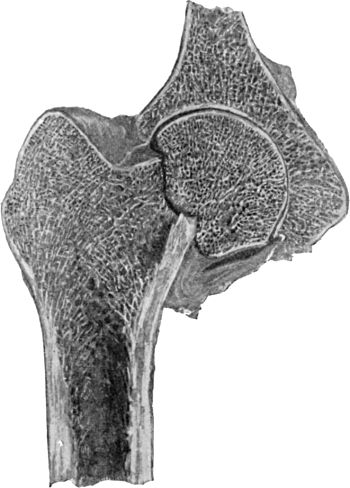

| 119. | Arthritis Deformans, showing erosion of Cartilage and lipping of Articular Edge of Head of Femur | 225 |

| 120. | Upper End of Femur in advanced Arthritis Deformans of Hip | 226 |

| 121. | Femur in advanced Arthritis Deformans of Hip and Knee Joints | 227 |